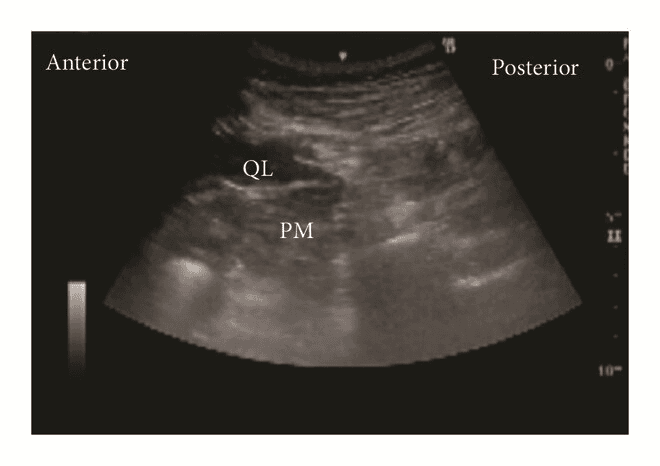

Задня QL-блокада (тип 2 QLВ, QLB2)

Для QLВ2 конвексний/лінійний датчик розташовують в поперечній площині по середньоаксилярній лінії та зміщують назад, як і при QLB1, доки не стане видимим задній край квадратного м'яза попереку. Голку вводять in-plane з латеральної сторони датчика до моменту, коли її кінчик опиниться біля заднього краю m. quadratus lumborum. Місцевий анестетик вводять в середній шар тораколюмбальної фасції поблизу поперекового міжфасціального трикутника (LIFT). Правильне розміщення кінчика голки має призвести до поширення місцевого анестетика вздовж середнього шару fascia thoracolumbalis до паравертебрального простору.